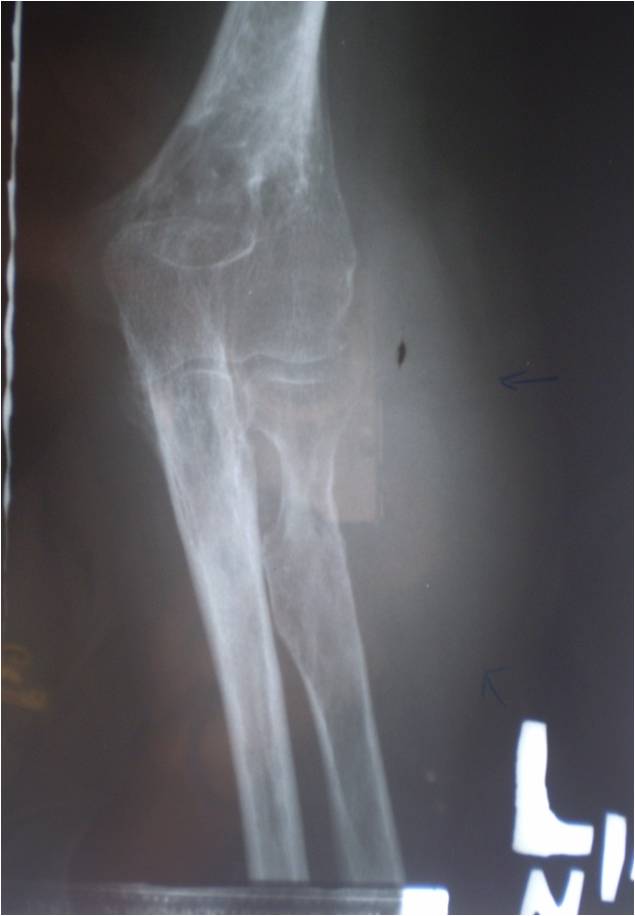

disimpulkan tidak tampak proses metastase pada paru-paru dan tulang (Gambar 3). Sedangkan foto antebrachii proyeksi AP/Lateral kiri dan foto Elbow proyeksi

AP/Lateral kiri, disimpulkan sebagai suatu primary

soft tissue tumor elbow kiri (Gambar 4,5).

Gambar 5: (Foto Elbow proyeksi AP/lateral

kiri): (A) Trabekulasi

tulang tampak porotik,tidak tampak lesi litik/blastik, tidak tampak destruksi korteks tulang. (B) Tampak massa jaringan lunak pada

regio elbow kiri dengan komponen kalsifikasi

di dalamnya (panah).

paru-paru dan tulang-tulang. Sedangkan pada foto Elbow kiri proyeksi AP/Lateral

tampak adanya suatu massa jaringan lunak dengan gambaran tulang yang porotik

disertai kalsifikasi pada massa jaringan lunak tersebut. Pada literatur

disebutkan gambaran radiologi konvensionalnya disamping adanya gambaran massa

jaringan lunak dan kalsifikasi (oleh karena adanya proses mineralisasi dari

tumor) juga disebutkan adanya suatu proses erosi superfisial, reaksi periosteal

serta invasi ke tulang, sedangkan pada kasus ini tidak ditemukan adanya

destruksi atau invasi ke daerah tulang-tulang disekitarnya. Pada pencitraan dengan MSCT 64 slices dan CTA